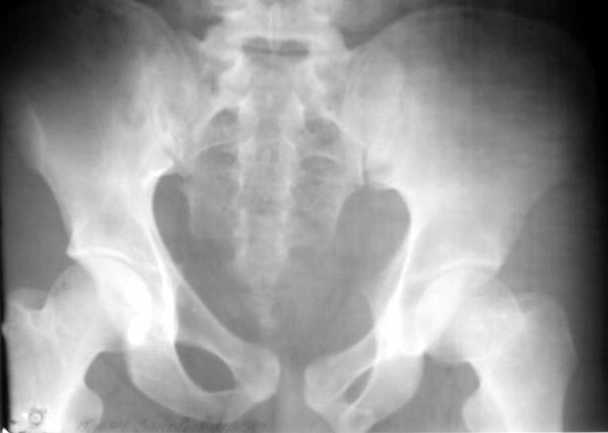

Согласно договоренности посылаю R-граммы

Во-1-х, там справа виден заголовочек "Файл-вложение", но раз трудности - переложил еще и прямо в собщение.